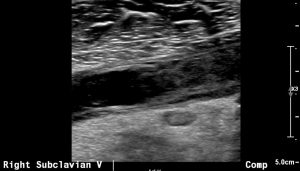

When a patient presents with an acute clot, imaging is usually done with duplex ultrasound. It is a highly sensitive test in experienced hands. Acutely, you will find a subclavian vein thrombus that will often extend to the axillary vein:

Venography is recommended in two instances. First, if the diagnosis is suspected, but proof was not obtained otherwise. For instance, when the duplex is inconclusive. The second use for venography, of course, is during a procedure. Venography often reveals venous collaterals, suggesting chronic sub-total compressions have been present. Furthermore, venography can be performed when the hand is in the neutral position or abducted. If extrinsic compression is visible, that suggests Paget Schroetter. Surprisingly CT and MR are not well suited imaging modalities for diagnosing Paget Schroetter, despite their obvious capabilities in diagnosing clot per se.